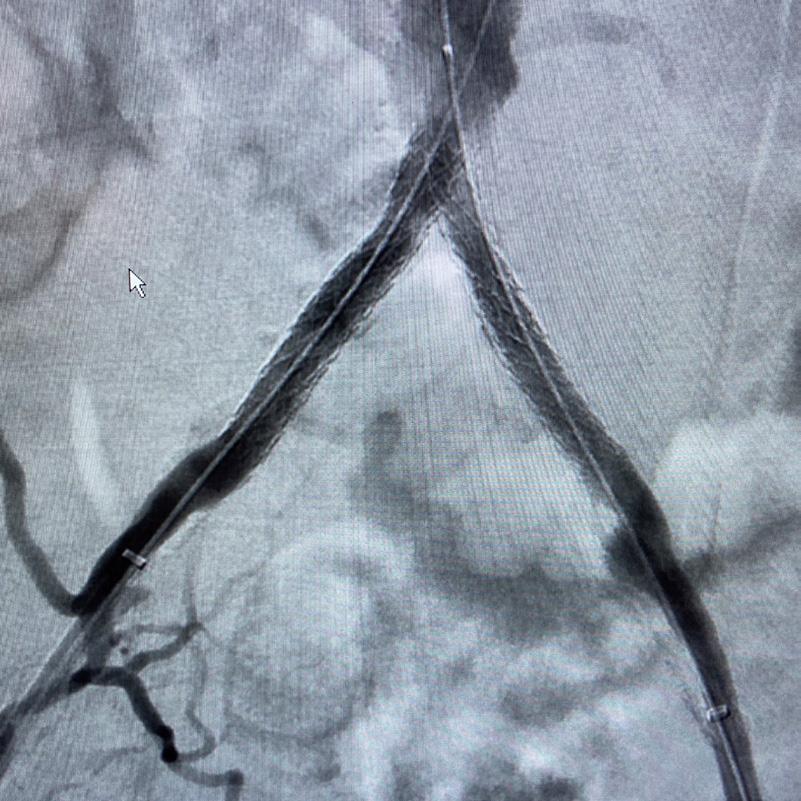

Case 2: The Shockwave M5+ tackles 90% stenosis of the distal SFA

The patient is a 75-year-old man with a history of hypertension, hyperlipidemia, CAD, chronic kidney disease and diabetes mellitus, who presents with a non-healing wound of the right lower extremity for three months.

He had undergone diagnostic work—his ankle-brachial index (ABI) was found to be 0.73 with a toe pressure of 50mmhg, and a duplex ultrasound revealed a densely calcified superficial femoral artery (SFA) stenosis of 90%.

He was taken to the cath lab and underwent a right lower-extremity arteriogram. This confirmed a 90% stenosis of the distal SFA, with normal three-vessel run off.

Due to the heavy calcium, we opted for a Shockwave M5+ 6x60mm and delivered 200 pulses to the lesion. There was no appreciable residual stenosis at the completion of the procedure, and his post-procedure ABI improved to 1.

Figure 1. Pre-procdural CTA Figure 4. Graft delivery Figure 1. Pre-procedural angiogram Figure 2. Pre-procedural angiogram Figure 5. Final angiogram Figure 2. IVL treatment angiogram Figure 3. Post-IVL angiogram Figure 6. Post-procedural CTA Figure 3. Final angiogram